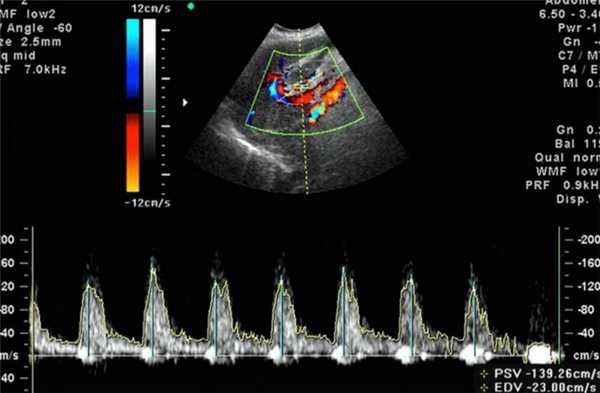

В зависимости от применяемых режимов одновременно выделяют: дуплексное и триплексное УЗГД. Как правило, для оценки внутриутробного состояния плода используют дуплексную допплерографию. При нем обычное серошкальное УЗИ сочетается с одним из режимов допплерографии, который в режиме реального времени передает изображение.

При триплексном сканировании режим УЗИ объединяется с режимом допплерографии и с цветным картированием кровотока, что позволяет оценить анатомию сосуда и его проходимость.

Для обследования используется такой же ультразвук, как и при обыкновенном ультразвуковом исследовании. Отличие заключается в особом датчике, работающем на основе допплеровского эффекта, и интерпретации полученных данных. При исследовании фиксируются ультразвуковые волны, отраженные не от статичных тканей, а от подвижных объектов - клеток крови, в результате чего частота отраженных лучей сильно изменяется в сравнении с изучаемыми. Аппарат обрабатывает полученные данные и создает двухмерное цветное изображение. Благодаря этому возможно оценить скорость и направление кровотока, анатомию и проходимость сосудов.

- Цветное картирование - состояние даже мельчайших сосудов и их проходимость кодируется цветом.

Расшифровка результатов допплерометрии плода

Оценка состояния кровоснабжения с помощью допплера формируется на основе следующих показателей:

- Систоло-диастолическое отношение - отношение максимальной и минимальной скорости кровотока;

- Индекс резистентности - отношение разницы максимальной и минимальной скорости кровотока к максимальной в период сжатия;

- Пульсационный индекс - отношение разницы максимальной и минимальной скорости кровотока к средней скорости за полный цикл сердца.